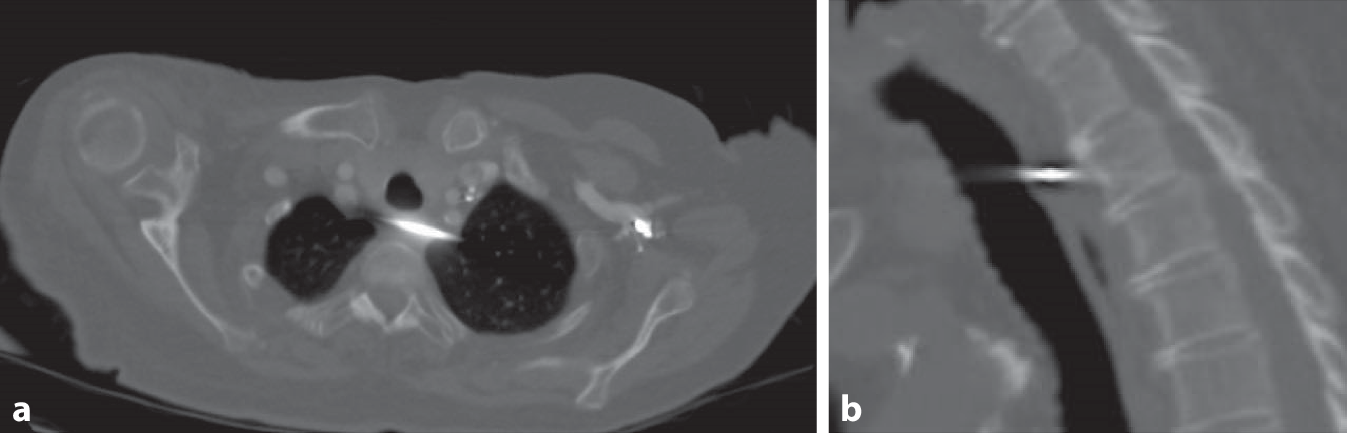

Die primäre operative Versorgung erfolgte in einem externen Krankenhaus mittels direkter K‑Draht-Osteosynthese. Röntgenologisch zeigt sich, dass die Enden der K‑Drähte nicht umgebogen wurden. Zudem kann eine korrekte, intraossäre Lage in beiden Frakturfragmenten nicht sicher belegt werden, da den Autoren nur eine Ebene vorliegt (Abb. 1). Allgemein wies die Patientin folgende Nebendiagnosen auf: arterielle Hypertonie, COPD, Diabetes mellitus und chronische Niereninsuffizienz.

Abb. 1

Postoperative Bildgebung des rechten Schultergelenks (Liegendaufnahme). Operative Versorgung mittels zweier K‑Drähte. (Aufnahmen aus externem Krankenhaus)

Einzelne Fallberichte über schwerwiegende Komplikationen, insbesondere durch Drahtmigration nach Versorgung einer lateralen Clavicula-Fraktur mittels K‑Draht existieren bereits [912]. Trotz dieser katastrophalen Komplikationen wird diese Technik weiterhin verwendet [710]. Neben der im Fall, erneut beschriebenen, Drahtmigration in „innere Organe“, ergibt sich ebenfalls ein schlechteres klinisches Ergebnis durch eine höhere Rate an Pseudarthrosen und Osteolysen im lateralen Frakturfragment [8]. Zur Verdeutlichung der komplexen Komplikationen berichten wir über eine Patientin, bei der die Drähte nach Osteosynthese sekundär zweizeitig disloziert sind. Diese kombinierte mediastinale und intrapulmonale Drahtfehllage stellte für die Patientin eine besondere Gefahrenkonstellation dar. In dem vorgestellten Fall wurde die Migration des Drahtes erleichtert, da die Enden nicht umgebogen wurden. Auch liegt den Autoren keine Bilddokumentation vor, welche die korrekte, intraossäre Lage in beiden Frakturfragmenten beweist, sodass eine bereits primäre Drahtfehllage nicht ausgeschlossen werden kann (Abb. 1). Eine adäquate Versorgung hätte eine röntgenologisch gesicherte K‑Draht-Transfixation des AC-Gelenkes und der Fraktur beinhaltet.